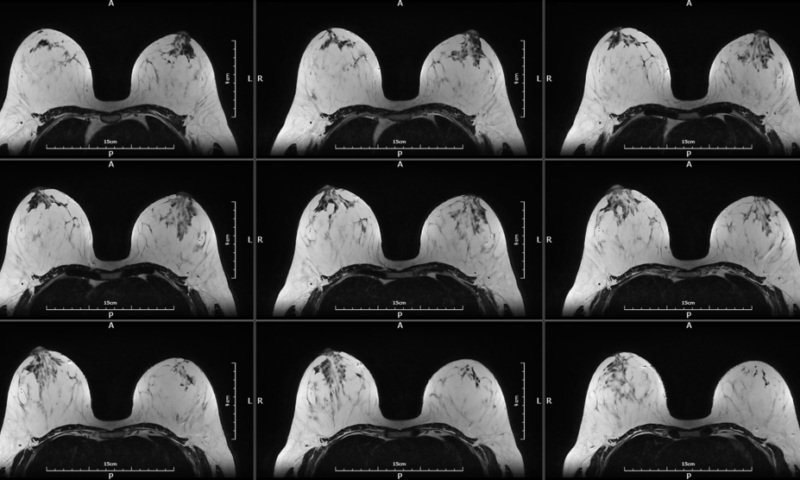

The EMMA 1.5T MRI is designed to offer breast imaging centers a new adjunctive tool to their current equipment options. Emma is a whole body MRI with dedicated breast coils for exclusive high-quality imaging.

In collaboration with leading breast cancer centers and following new published trends, the EMMA system extends MRI’s strong diagnostic utility with rapid and cost-effective – optimal breast MRI screening exams (AB-Breast MRI). It’s a cutting-edge, humanistic and affordable MRI Breast Scan.

Customized breast coils with 3 cup-size to deliver exceptional breast images.